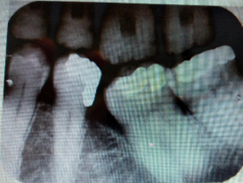

A woman comes with a complaint of bad taste and feels dull ache in the 36 37 regions specially after she eats meat and when food gets stuck. Ootherwise no pain when drinking. You took bitewing Xray, and you can see multiple composite restorations and caries. You also can see an open contact between 36 and 37 with 36 having secondary caries while 37 was mesially tilted with slight vertical bone loss seen mesially.

Bitewing taken: There are lot of caries x ray was given.

X-ray bitewing showing multiple composites.

- upper 27, 26, 25, 24 and

- lower 37, 36 (with recurrent caries in the filling), 35, 34